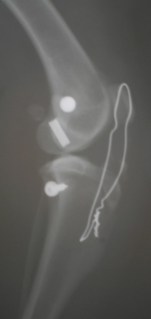

![]() |

| Μετεγχειρητική ακτινογραφία |